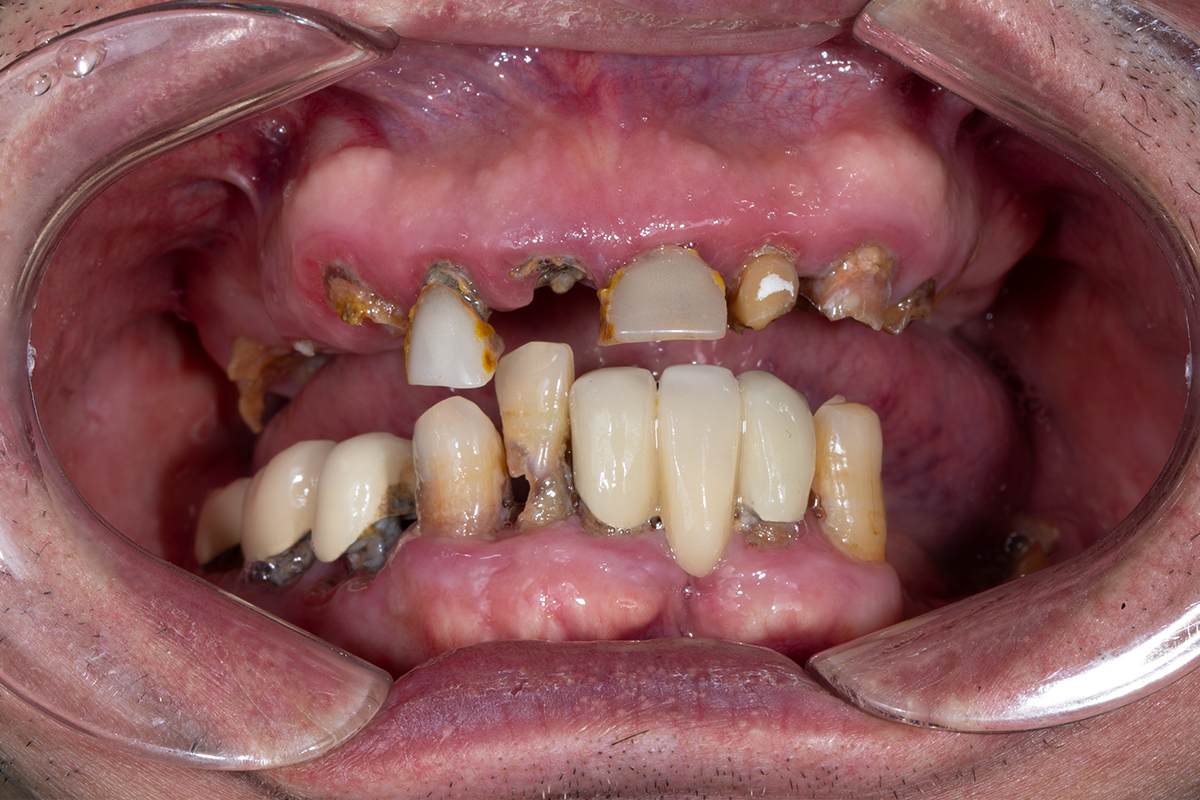

- Mất nhiều răng hoặc toàn bộ răng lâu năm, có sử dụng các phiện pháp khắc phục răng mất như hàm giả tháo lắp, cầu răng sứ nhưng dùng hàm tháo lắp thì tuột, cầu răng sứ dài lung lay hỏng gây đau.

Những người mắc nhiều yếu tố nguy cơ thường đi liền với viêm quanh răng và cả tình trạng tiêu xương tụt lợi.